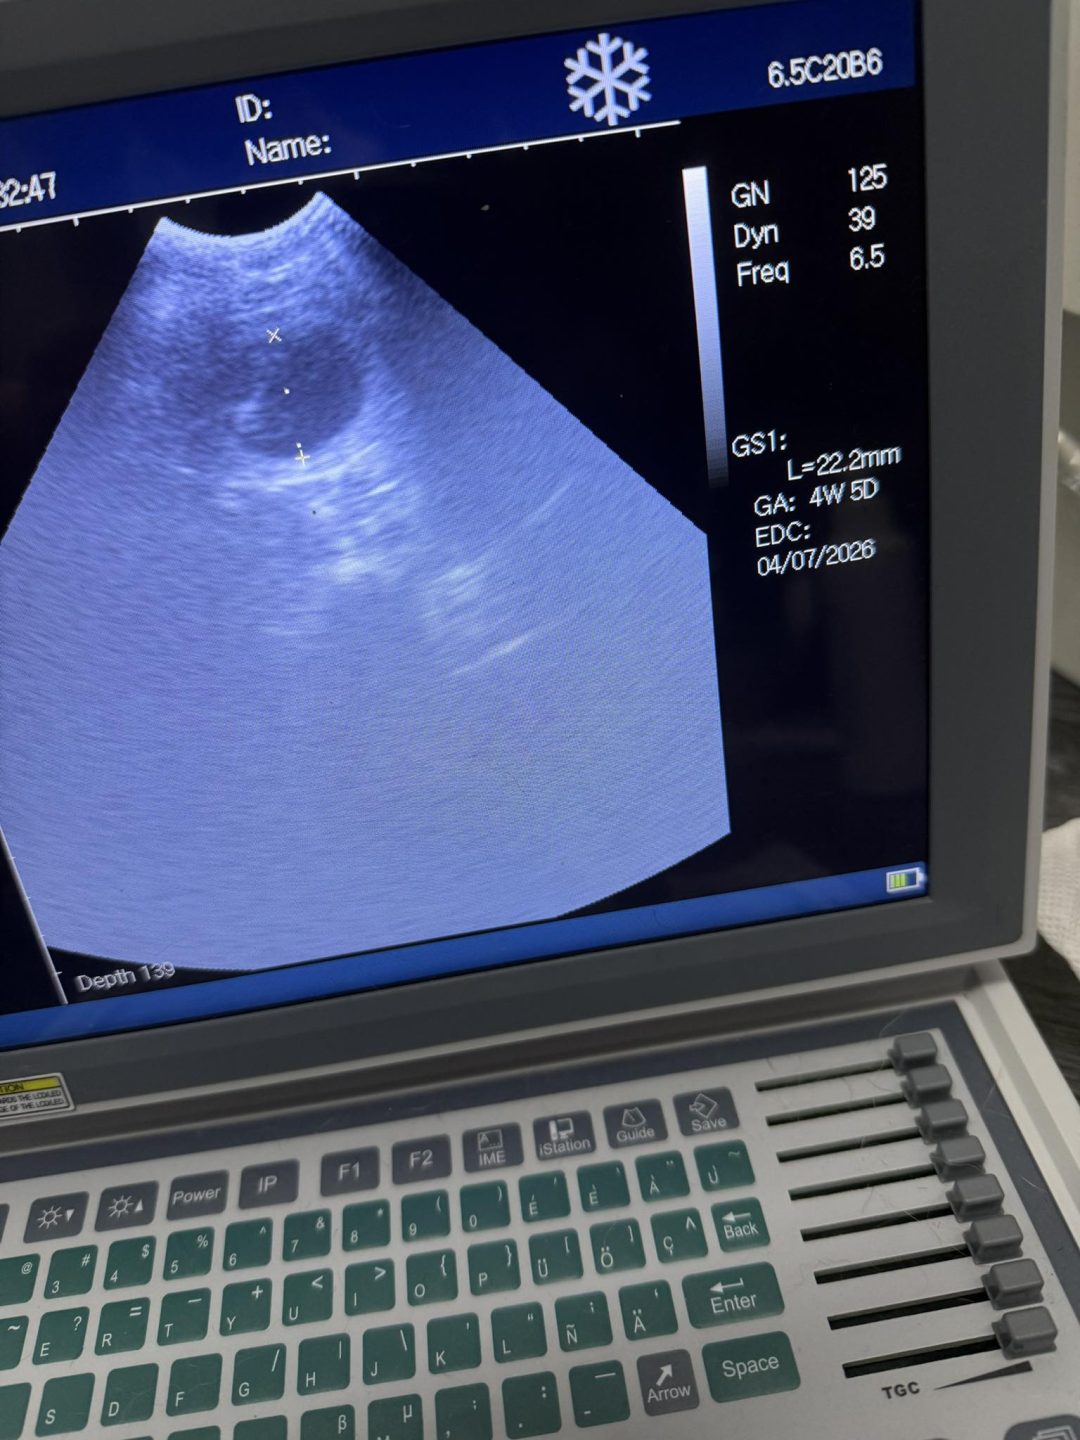

A few confirmation ultrasound scans were carried out today at Preston’s K9 fertility services

It’s such a pleasure letting these stunning girls’ owners know that their girl is in pup

Estimated due date and pup counts given.